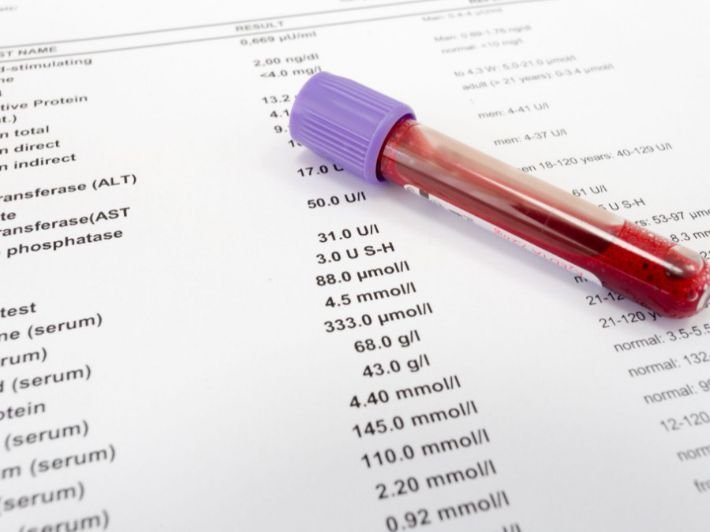

الفحص الشامل

الفحوصات الشاملة

الفحص الطبي الشامل – لأن الوقاية أفضل من العلاج

في Zara BKK، نمنحك فرصة الاطمئنان على صحتك من الداخل، من خلال برامج فحص طبي شامل دقيقة ومتكاملة، صُممت لتكتشف المشكلات الصحية قبل ظهور الأعراض.

لماذا الفحص الشامل مهم؟

- لاكتشاف الأمراض في مراحلها المبكرة

- للاطمئنان على القلب، الكبد، الكلى، الغدد، الدم، والهرمونات

- لفهم مؤشرات الجسم الحيوية واتخاذ قرارات صحية

- للمسافرين، كبار السن، رجال الأعمال، أو من يهتمون بصحتهم بوعي

ماذا يشمل الفحص؟

- تحاليل دم شاملة (السكر، الدهون، الكبد، الكلى، الفيتامينات، السرطانات…)

- تحليل البول والبراز

- تخطيط القلب ECG

- تصوير بالموجات فوق الصوتية (أعضاء البطن – الغدة الدرقية)

- أشعة صدر / أشعة مقطعية (حسب الباقة)

- استشارة طبية مع طبيب مختص لمعرفة النتائج

فحص الفيتامينات

فحص الفيتامينات – لأن صحتك تبدأ من التغذية الداخلية

هل تشعر بالتعب بدون سبب؟ سقوط الشعر؟ ضعف المناعة أو تركيزك منخفض؟

قد يكون السبب نقص في الفيتامينات والمعادن الأساسية في جسمك، حتى لو كنت تتناول طعامًا جيدًا.

في Zara BKK، نوفّر لك فحصًا دقيقًا للفيتامينات والعناصر الغذائية لتحديد ما يحتاجه جسمك بدقة.

🔍 ما يشمله فحص الفيتامينات:

- فيتامين D – لصحة العظام والمناعة

- فيتامين B12 – للطاقة والأعصاب

- فيتامين C – للمناعة وتجديد الخلايا

- فيتامين A – للبشرة والرؤية

- فيتامين E – لمضادات الأكسدة والبشرة

- حمض الفوليك – للنساء والحوامل

- معادن مهمة: الحديد، الزنك، المغنيسيوم، الكالسيوم

🛠️ ماذا نقدم لك؟

- تحاليل مخبرية دقيقة

- استشارة مع طبيب أو أخصائي تغذية

- خطة دعم غذائي أو مكملات حسب النقص

- إمكانية دمج الفحص ضمن الفحص الشامل أو مكافحة الإرهاق